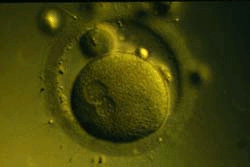

Зигота: ДНК сперматозоида уже внутри яйцеклетки. Скоро произойдет слияние отцовской и материнской половин генетической программы и начнется первое деление клетки. Так происходит оплодотворение.